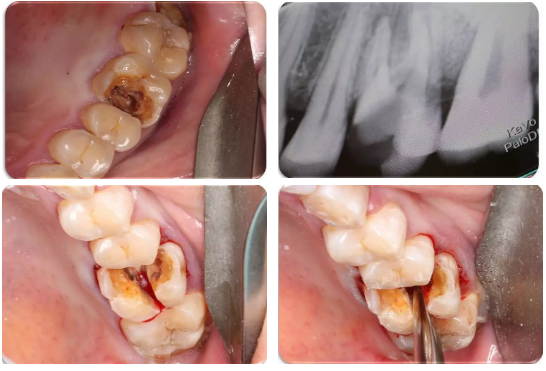

5、下颌第三磨牙的阻力分析及手术设计;

怎样正确读懂X线片和CBCT上关于下颌第三磨牙的信息

下颌阻生第三磨牙的阻力分析、解除各步骤要点

通过病例讲解各类下颌阻生第三磨牙的微创拔除方法

通过病例分析手术中遇到问题怎样解决